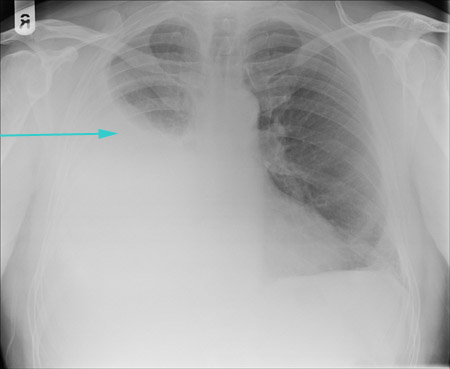

CXR showing large right pleural effusion

From the collection of Dr Kathryn Bateman; used with permission